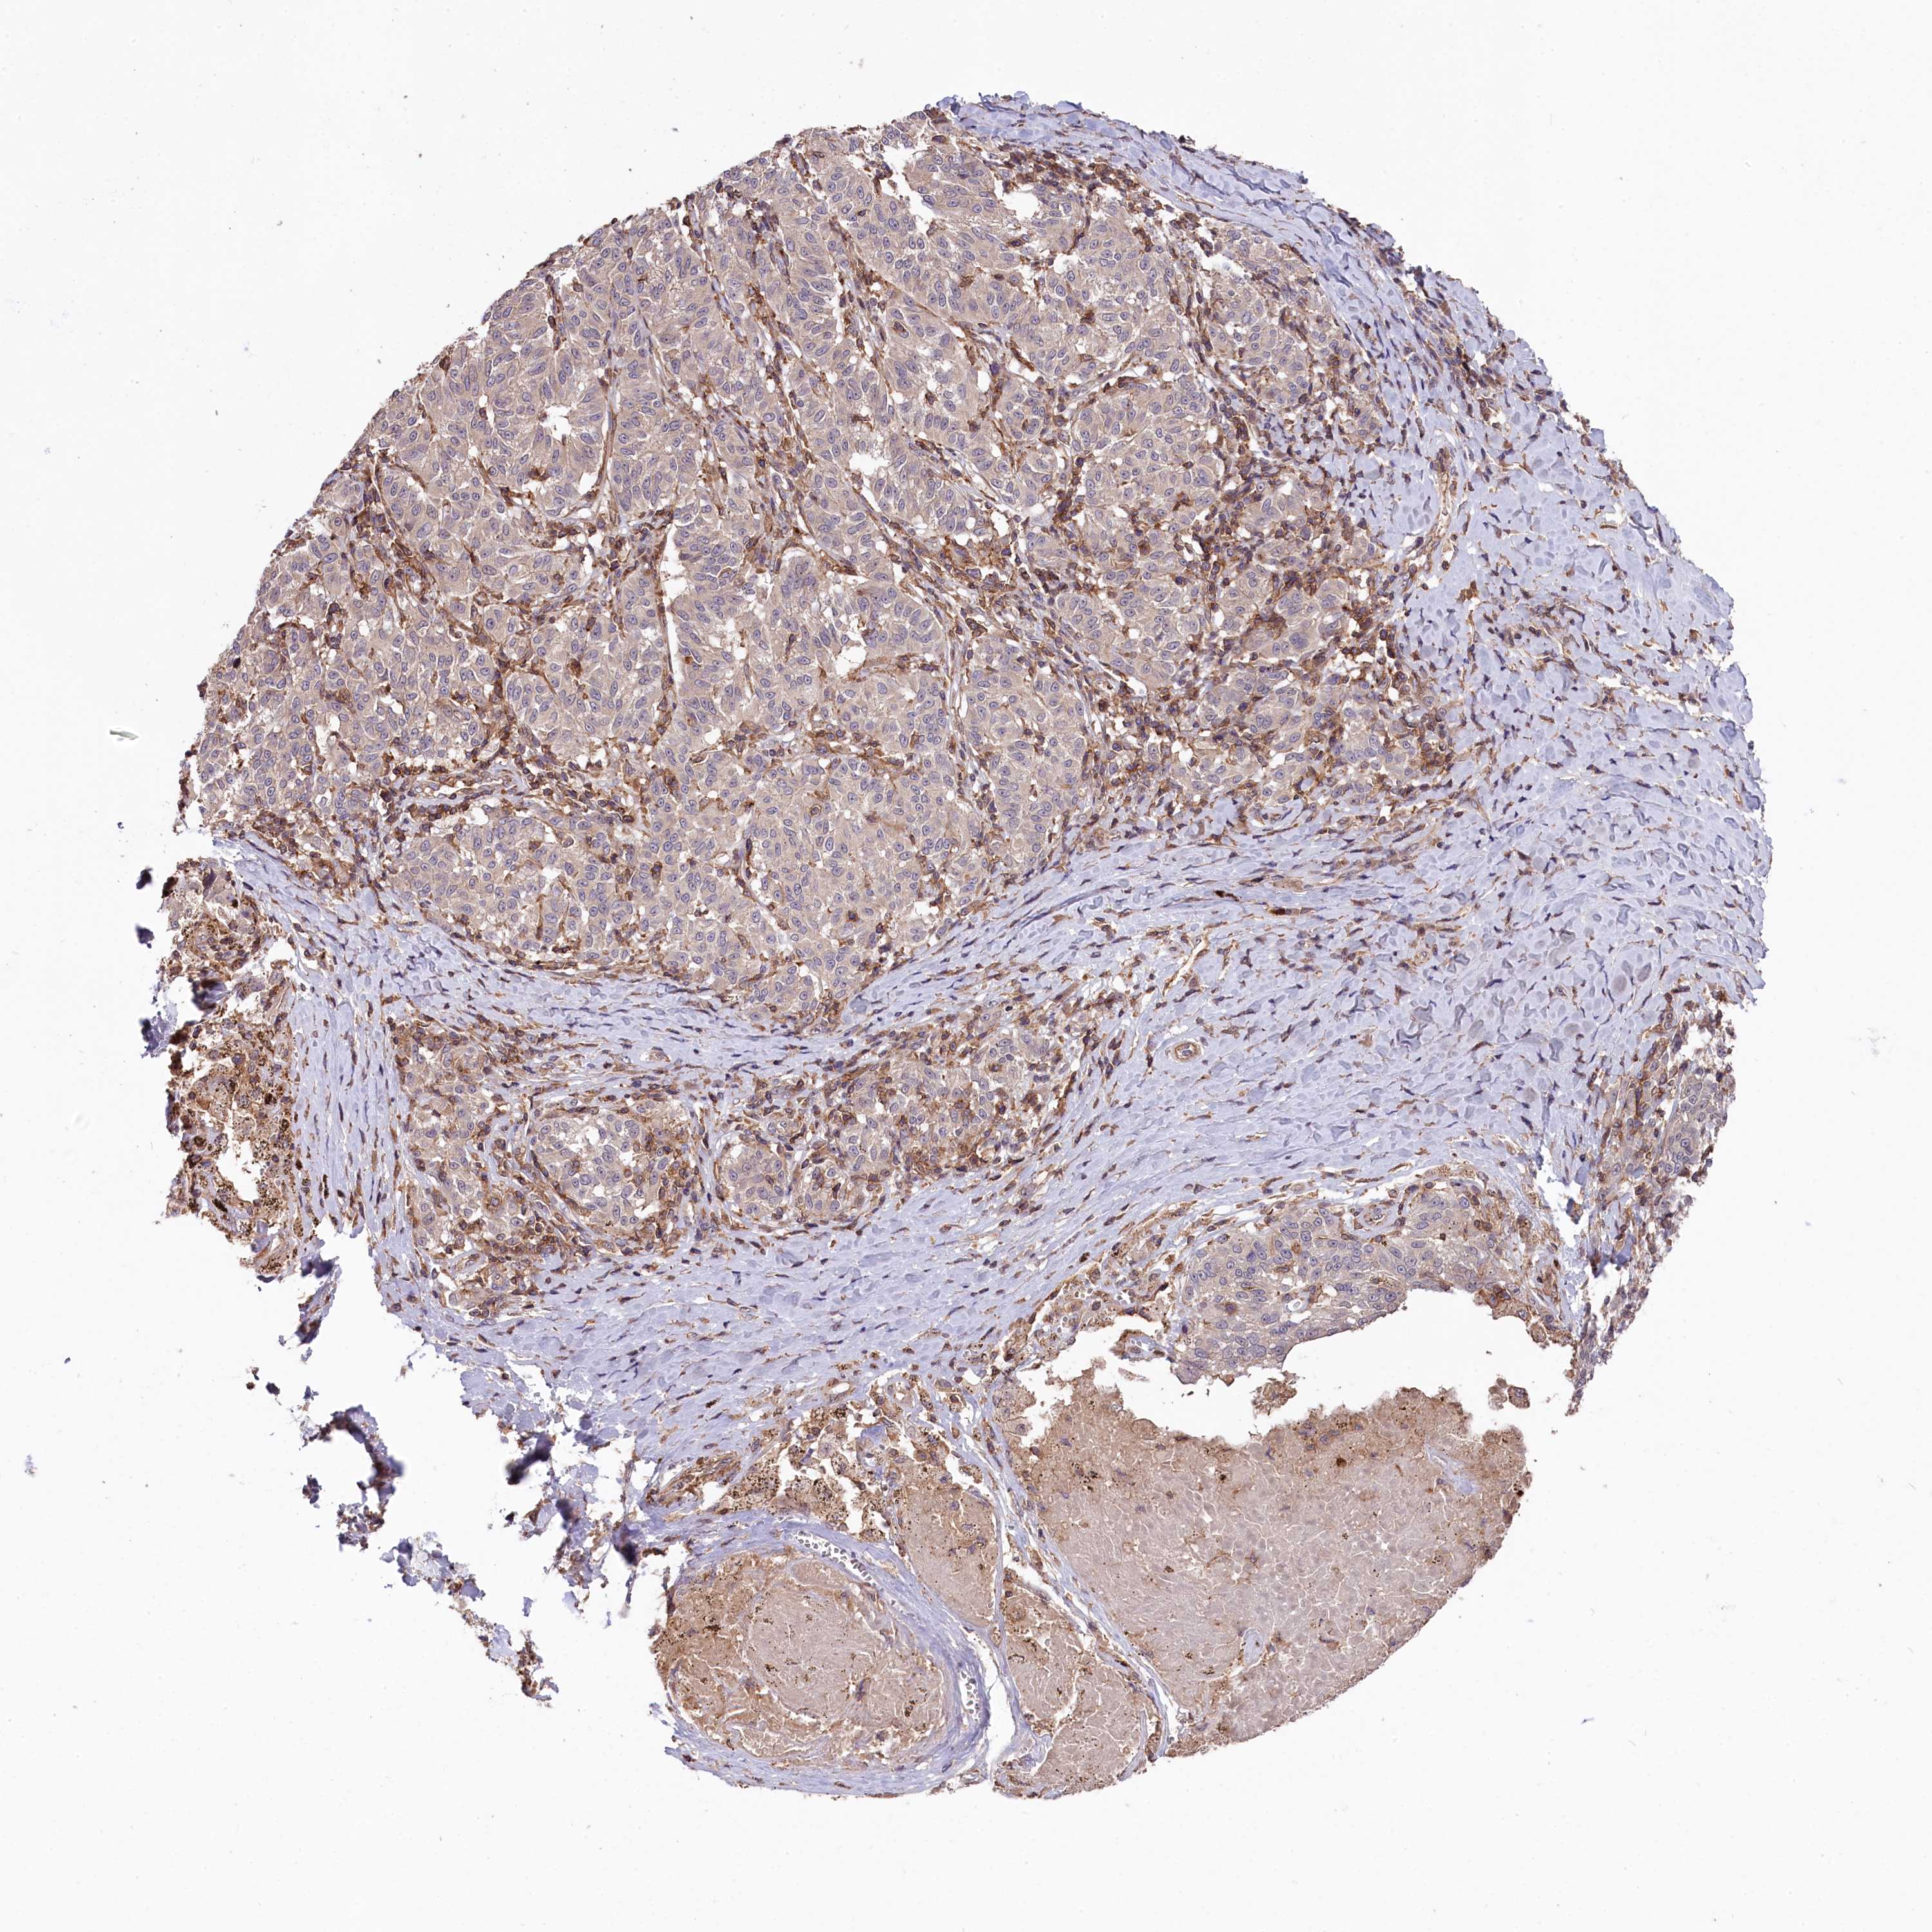

MELANOMA - Protein expressioni

A mouse-over function shows sample information and annotation data. Click on an image to view it in a full screen mode. Samples can be filtered based on level of antibody staining by selecting one or several of the following categories: high, medium, low and not detected. The assay and annotation is described here.

Antibody stainingi

Antibody staining in the annotated cell types in the current human tissue is reported as not detected, low, medium, or high, based on conventional immunohistochemistry profiling in selected tissues. This score is based on the combination of the staining intensity and fraction of stained cells.

Each image is clickable and will lead to virtual microscopy that enables deeper exploration of all samples and also displays staining intensity scores, fraction scores and subcellular localization as well as patient and tissue information for each sample.

Antibody HPA040439

Staining

High

Strong

>75%

Nuclear

Malignant melanoma, Metastatic site